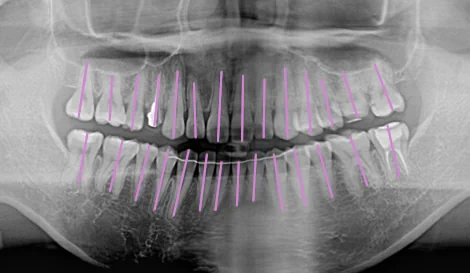

本質的な矯正は、歯茎の上に見えている部分の歯並びだけでなく、

歯茎の下の歯根がキレイに並んでこそ実現します。

このケースでは、並行に並んでいなかった歯根からしっかりと矯正を行い、

1年弱の矯正期間で、歯根まで並行にならぶキレイな歯並びとなりました。

歯根がきれいに並んでいることで、歯周病のリスクを抑え、長持ちする歯へと改善されました。